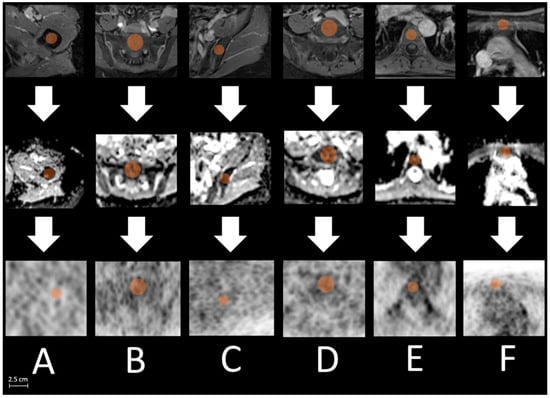

2.3. Image Analysis